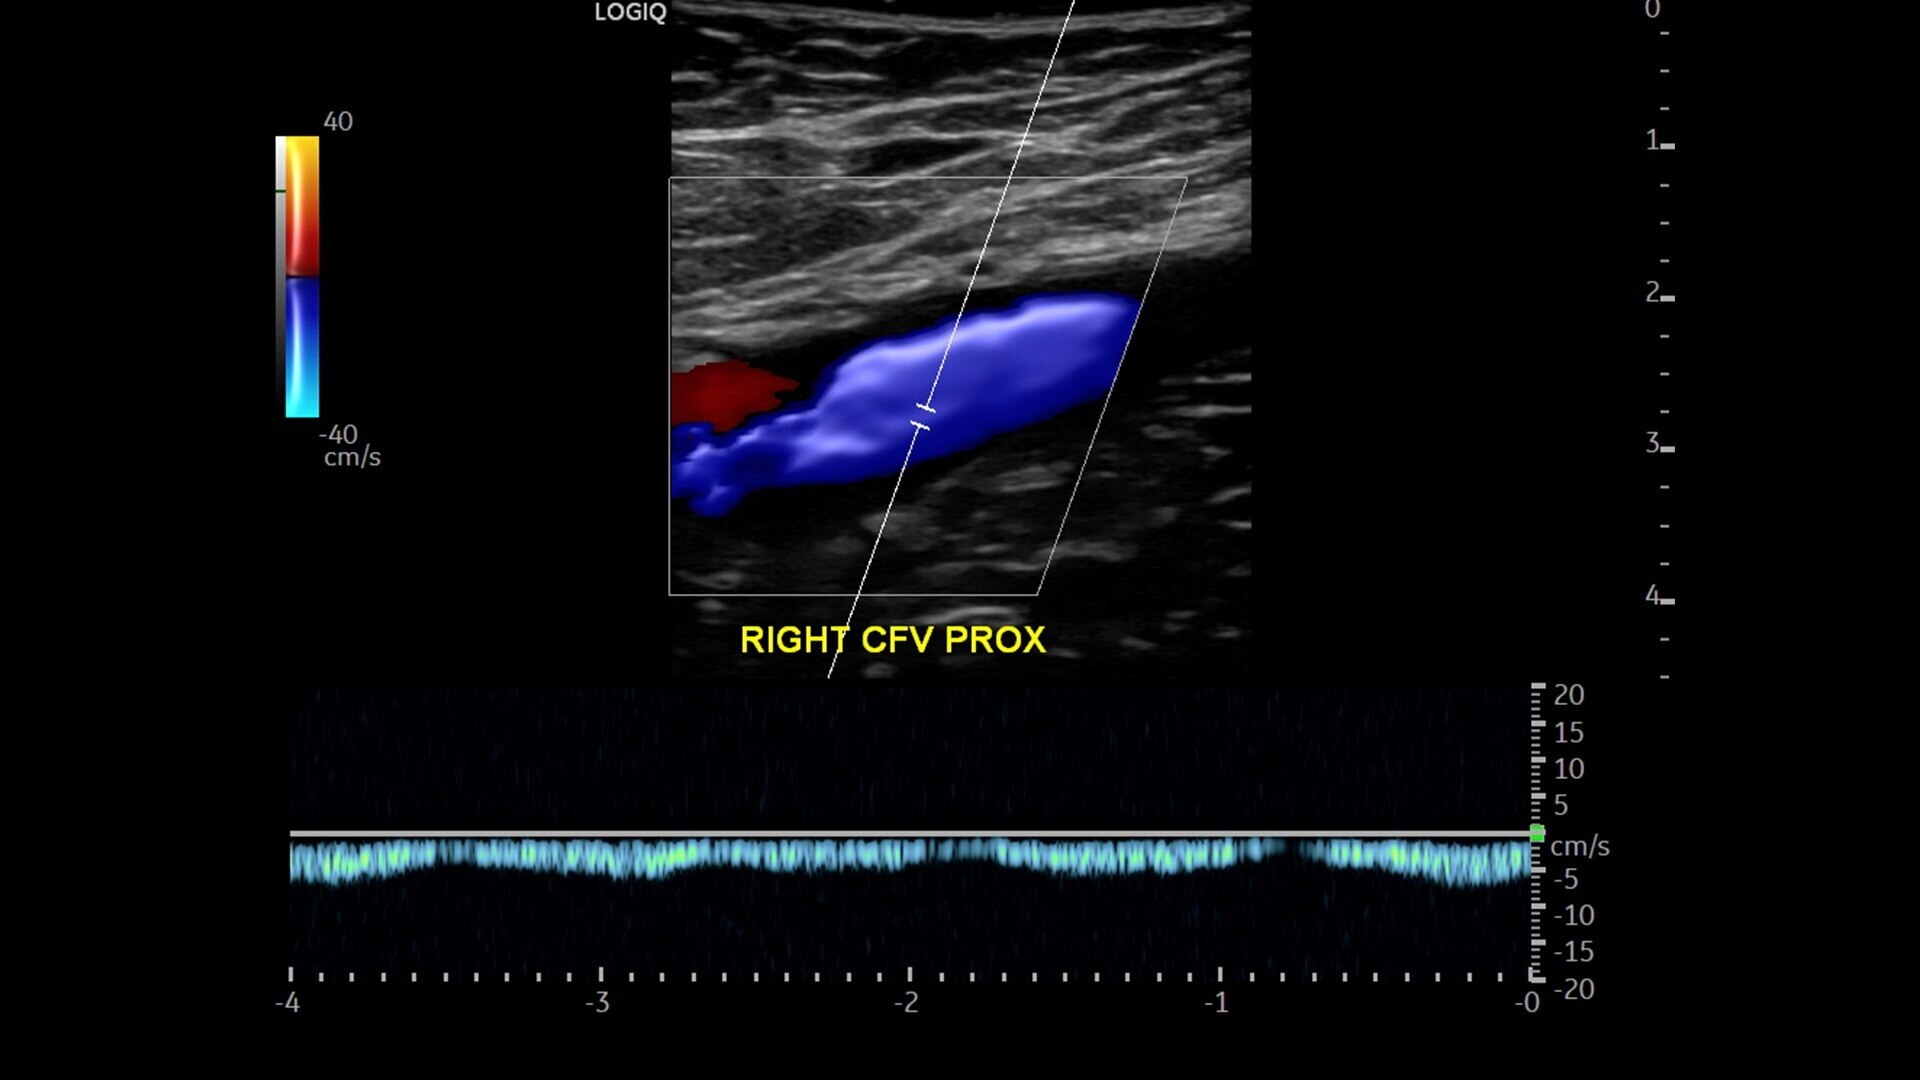

• Advanced flow modes give you the flexibility, from large vessels to fine microvascular detail, to visualize blood flow with precision

• Auto Abdominal Color Assistant 1.0: Automatically detects what anatomy is being scanned and selects the correct abdominal flow shortcuts in real time